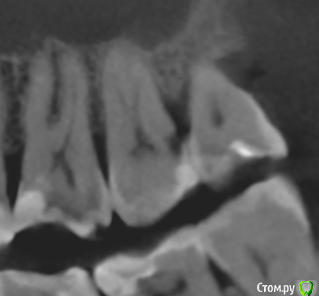

apex007 Опубликовано 26 января, 2021 Поделиться Опубликовано 26 января, 2021 Добрый день! 27 и 28 зубы немного развернуты в сторону щеки . В 27 серьезные разрушения со стороны 28, на уровне десны и под десну . Между 27 и 28 глубокий карман, видимо, из-за попадания остатков пищи в карман и возник кариес 27. Сейчас 27 вскрыт, врач предлагает удалить 28, чтобы можно было немного оттеснить десну и восстановить дистальную стенку 27. При этом 27 пришлось депульпировать, сейчас каналы еще не закрыты. Правильно понимаю, что удаление 28 приведет к ускорению рецессии кости и ухудшению прогноза для 27? Следует ли удалять 28 сейчас или восстановить 27 как получится и посмотреть на результаты эндодонтии через год (в 27 сложные каналы ), а карман промывать ирригатором? Фото по состоянию до начала лечения. Ссылка на комментарий